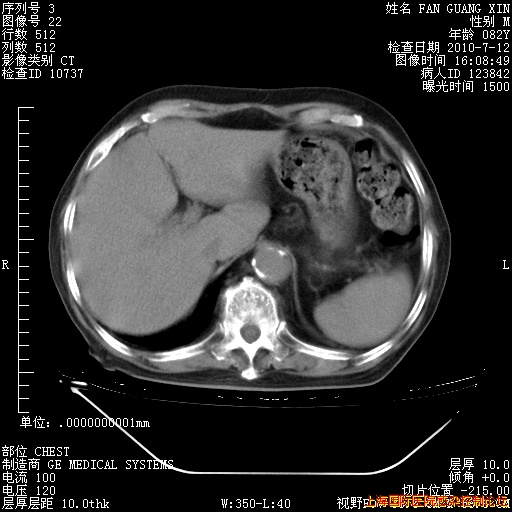

今天复查CT

整整相隔30天的肺部CT好像有所好转啊。甲强龙减量第3天,需要观察体温。